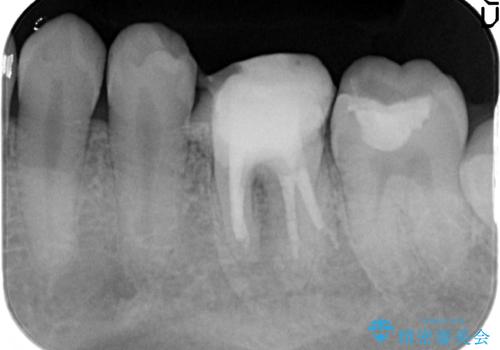

放置してしまった歯 根管治療からの機能回復

- 放置してしまった歯が痛み、いよいよ耐えられなくなり来院されました。

根管治療の途中で放置してしまっていた歯を、最終的に機能回復できるよう治療を行っていきます。

- 13万円(仮歯・ファイバーコア・ジルコニアクラウン)費用は治療当時の料金となります